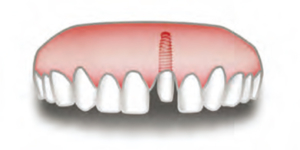

Impiantolo spesso era un pò svitato, ma quella volta diede il meglio di sè cominciando a muoversi, danzando, ballando, piroettando, ma sopratutto avvitandosi su se stesso come un vero ballerino…

Ma ad un certo punto successe l’imprevedibile.. durante l’ennesima piroetta Impiantolo scivolo’ giù dal palco infilandosi dritto dritto nella mandibola di uno spettatore rimasto a bocca aperta affascinato dalle sue acrobazie…

Gli otto nani rimasero in sette, mentre Impiantolo capi’ che si era avvitato troppo e non riusciva piu’ a uscire dalla bocca del malcapitato.